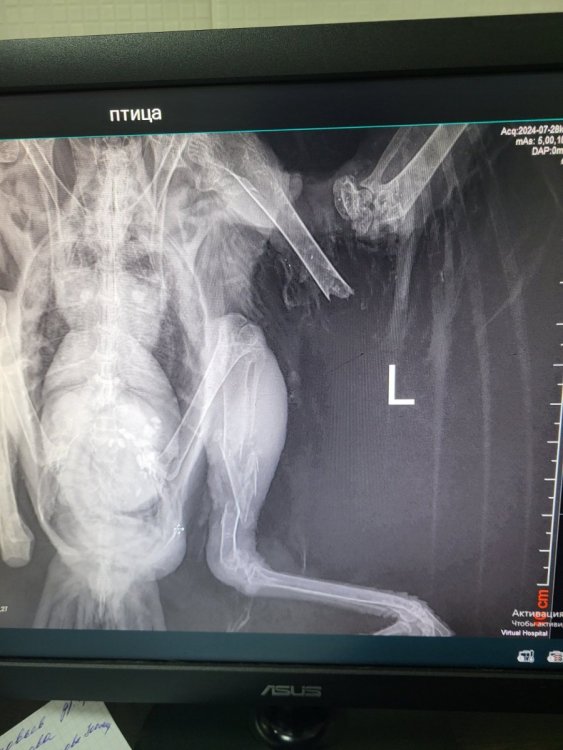

Здравствуйте. Подскажите, пожалуйста, нашли два дня назад грача, на вид уже взрослый. У него крыло и лапа сломаны. Сделали рентген.

У меня не хватит знаний, чтобы выходить птицу, в городе у нас орнитологов нет. Могу помочь с оплатой. Помогите найти волонтёра кто  выхаживает таких птиц?

20240728_185223.jpg

20240727_172152.jpg